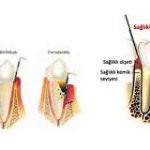

Periodontitis, diş eti ve diş çevresindeki dokuların kronik enfeksiyonu ile karakterizedir. Bu enfeksiyonlar sistemik inflamatuar yanıtı tetikleyebilir:

- Periodontal patojenler (ör. Porphyromonas gingivalis, Aggregatibacter actinomycetemcomitans) lokal inflamasyon yaratır.

- Günlük diş fırçalama, diş eti kanamaları veya periodontal cep derinliği ile bakteriler kana geçebilir.

3. Endotelyal disfonksiyon

- Periodontal enfeksiyonlar, endotelyal hücrelerde fonksiyon bozukluğu (endotelyal disfonksiyon) yaratabilir.

- Sonuç: damar sertliği ve hipertansiyon riski artar.